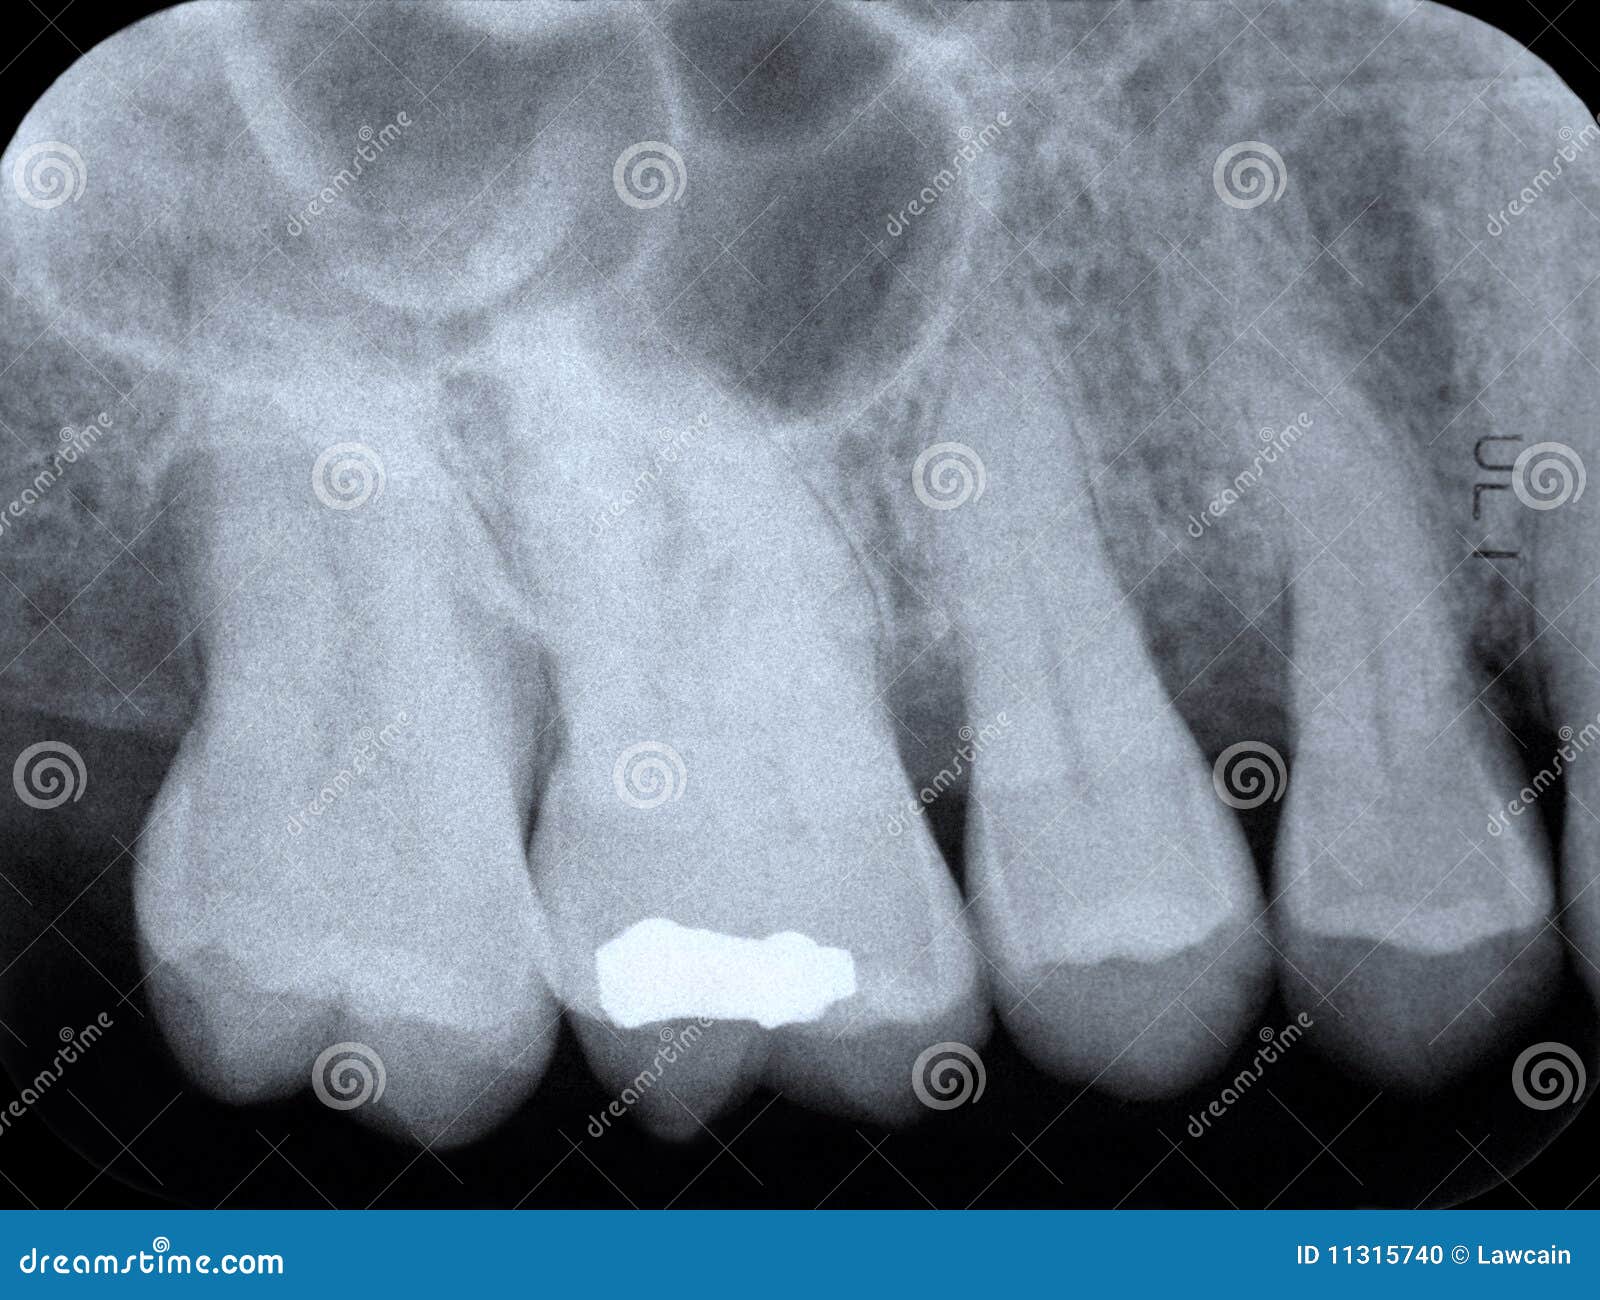

From www.dreamstime.com

Periodontal Xray stock photo. Image of dental, gingival 11315740 Periodontal X Ray radiographs are an integral component of a periodontal assessment for those with clinical evidence of periodontal destruction. The optimal projections for periodontal diagnosis in the posterior teeth are bitewing radiographs if. it is generally widely accepted that radiographs supplement clinical examination in establishing the diagnosis and guiding. A close consideration of the current approach to periodontal diagnosis compatible. Periodontal X Ray.